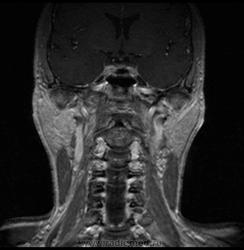

06.06.2011 МРТ - головы и шеи.

Пацентка 36 лет, с жалобами на припухлось в околоушной области справа.

В глубокой доле  правой околоушной железы  на фоне неизмененной паренхимы зона  гетерогенного по Т2, гипоинтенсивного по Т1  с единичными гиперинтенсивными включениями.При контрастировании- накопление контраста диффузное неоднородное и по периферии.Рискну предположить злокачественное образование ( аденокарцинома) с низкой степенью злокачественности( есть капсула, экспансивный рост).Сильно не расстреливайте.

Проблема в том, что перед челюстно-лицевым хирургом стоит распространенность любого объемного процесса, в данном случае все упирается в возмможную травму лицевого нерва и конечно же с дальнейшим его парезом, а ведь женщина  еще молодая. Образование имеет тонкостенную оболочку, по структуре неоднородно, с наличием кальцината, при этом МР-сигнал от окружающих анатомических структур(как костных так и мышечных) не изменен, т.е. об инфильтративном росте речи не идет, в какой то степени доброкачественное. В конкретном случае лицевой нерв с ретромандибулярной веной просто несколько оттеснен.

По гистологии аденома околоушной слюнной железы, но после удаления пока сохраняется парез лицевой мускулатуры, возможно временный.